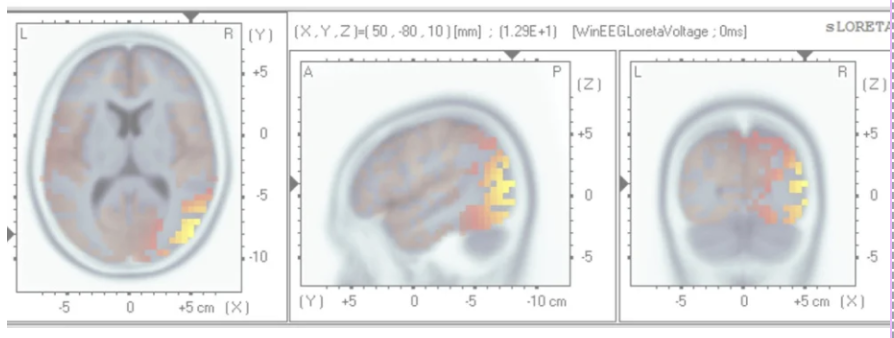

SLoreta Analysis.

Once frequency of interests have been selected, sLoreta analysis may be conducted to determine maximum z-scores, frequencies and source locations. In BrainDx analyses can be done separately for slice (typical) or volumetric sloreta (seen to the left). sLoreta is a solution to the EEG inverse problem that mathematically proposes to determine the source (or sources) of predetermined EEG activity. Volumetric sLoreta shows a distribution of sources with a maximum value determined as well.